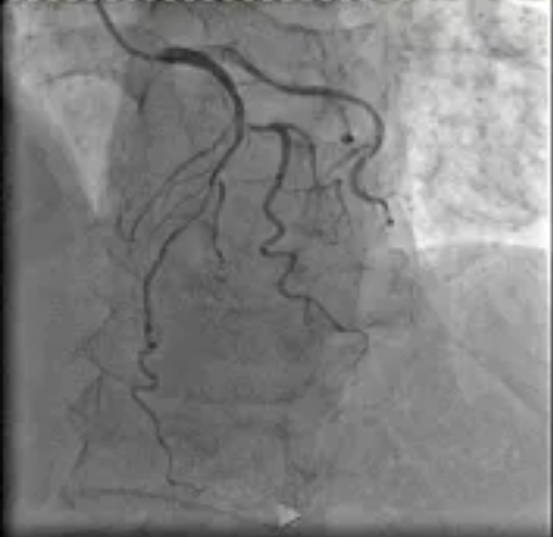

日前,我院阳逻院区心血管内科收治一名冠状动脉疾病患者,CT检查显示冠状动脉左前降支存在病变,最严重处狭窄达85%且伴有钙化。

在医院心血管内科主任李昌教授的指导下,阳逻院区心内团队运用冠状动脉血管内超声(IVUS)技术详细检查患者血管,发现主支血管狭窄程度处于临界状态,可暂时通过药物治疗来优化;分支血管严重狭窄,需要进行介入治疗。基于IVUS提供的精准信息,患者避免了不必要的支架植入,有效降低手术风险。这一精准化治疗方案,既减少患者创伤与经济负担,又降低术后并发症风险,为患者的健康提供了有力保障。

患者IVUS检查影像报告